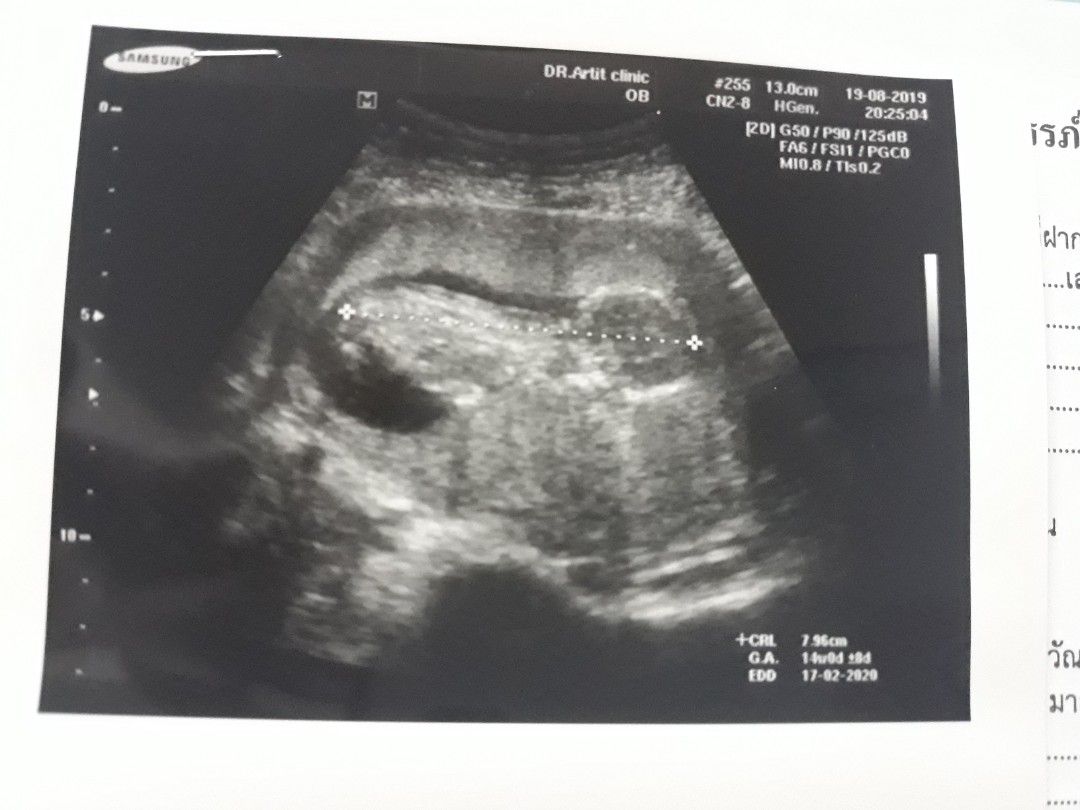

14wค่ะ